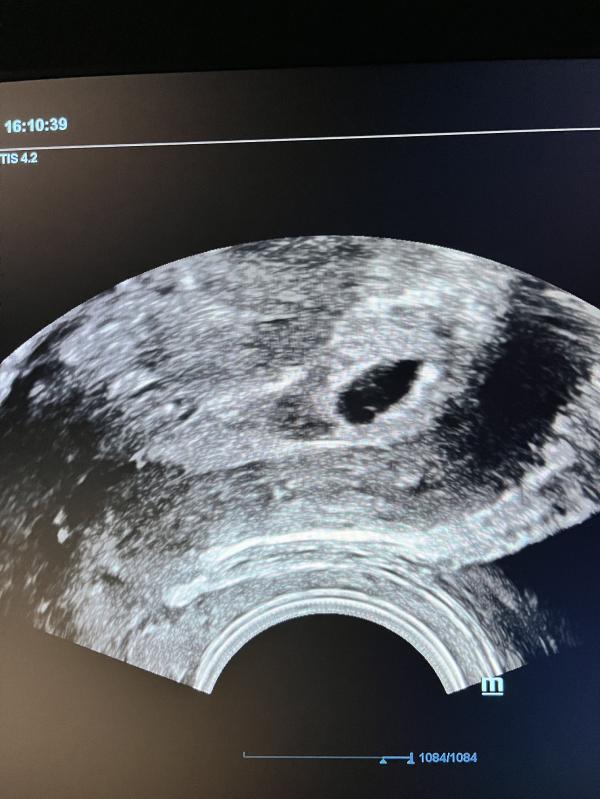

Срок 8.4

Замер на 7 неделе.Сердцебиения нет,смотрели на 2 узи сегодня.

Сколько у меня есть времени?Чтоб определиться где и что делать.пока в шоке.Сутки хоть можно никуда не бежать?